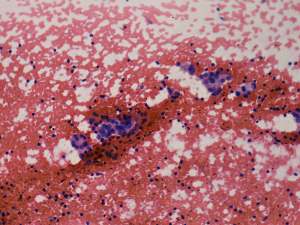

Aspiration cytology: There was no colloid in the background. Follicular cells occurred in microfollicles and compact clusters. Lymphocytes were also present in smaller number, even mixed with follicular cells. Grooves were found occasionally.

Histopathology disclosed Hashimoto's thyroiditis with several cystic areas but without any nodule.